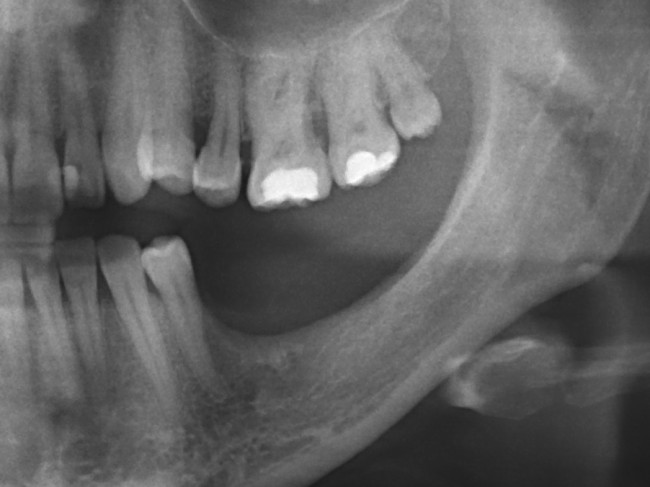

Итак, вот изначальная ситуация:

до лечения

Я понимаю, что данных на части панорамного снимка очень мало для правильной интерпретации клинической ситуации, но, с другой стороны, это позволит не перегрузить Вас информацией.

• боковой сегмент, отсутствуют три зуба: 35, 36, 37. Эти зубы удалены достаточно давно, развилась сильная атрофия костной ткани.

• верхние зубы, не имея антагонистов, выдвинулись вниз (зубоальвеолярное удлинение, т. н. «симптом Попова-Годона»).

• пациентке примерно 30 лет. То есть, вся жизнь еще впереди)).

Sketch94233528

Их несколько, они обозначены на снимке.

1. Значительная атрофия костной ткани, особенно по высоте. Решается: остеопластической операцией.

2. Дефицит слизистой оболочки почти всегда сопровождает атрофию кости. Следовательно, после имплантации (либо до нее) нам потребуется пластика десны. Я предпочитаю это делать на этапе установки формирователей десны.

3. Зубоальвеолярное удлинение в области зубов-антагонистов. Решается: ортодонтическим лечением.